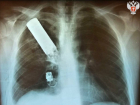

Осколок гранаты вытащили донецкие врачи из груди пациента: операцию проводили в бронежилетах и касках 20.06.2023 Здоровье